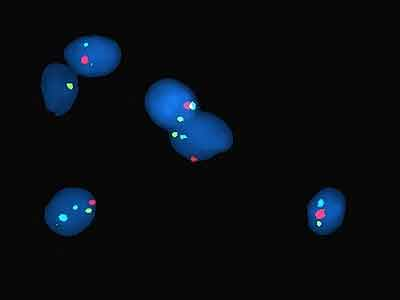

Наличие светящихся меток показывает, как много копий исследуемого гена находится в клетках, и где именно они расположены, в какой последовательности.  Исследованию подвергается сразу сотни сперматозоидов.